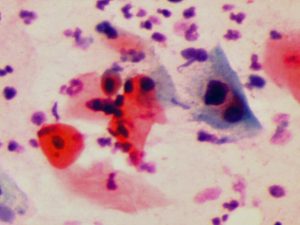

Mikroskop incelemesinde Human Papilloma Virüsü (HPV) nin rahim ağzı hücrelerinde yaptığı değişiklikler görülmektedir.

Pap smear testi ve HPV DNA testi için muayene sırasında rahim ağzından, rahim ağzı kanserinin en çok görüldüğü bölgeden (transformation zone) çubuk şeklinde, ince bir fırça yardımıyla akıntı örneği alınır(65,70,71). Bu akıntı örneğinde görülen hücrelerde HPV DNA’ sının varlığını tespit etmek için HPV DNA PCR testi yapılır, pap smear testinde de akıntı örneğindeki rahim ağzı hücreleri mikroskop ile incelenerek HPV enfeksiyonunun neden olduğu değişiklikler görülür(41,51,54,57,58,59,65,70,71,75,77,86,91).

Gözle görülemeyen, ancak mikroskop ile görülebilen hücre içinde bazı değişikliklere (Squamous Intraepithelial Lesion) (SIL) neden olmaktadır(35,36,41,43,49,51,54).

1- Bu hücresel değişiklikler ancak pap smear testi ile görülebilmektedir.